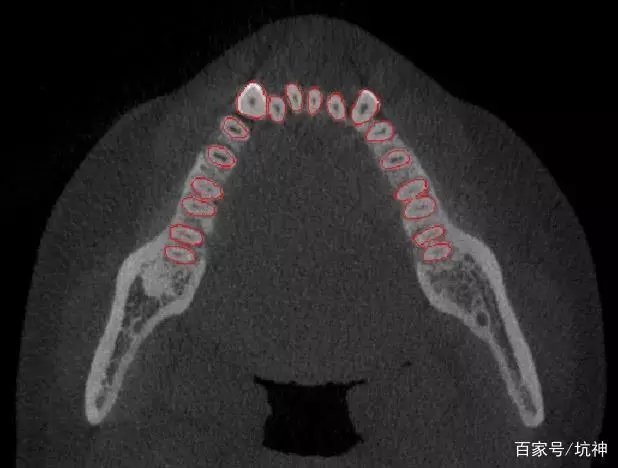

“Ortholink优领”个性化牙根功能△

它是通过机器的深度学习,用“机器判断+机器自动化操作”代替“主观判断+人工处理”,使用深度神经网络自动提取牙根数据、并完成牙根重建的一种智能化操作。

机器深度学习结果△

这项技术大大解放了劳动力,处理效率提高了300%,而且处理结果的精度更高,初步实现了人工到人工智能的转变!当人工智能概念与数字化正畸技术相融合,数字化技术便能从人的角度出发,想人之所想,让智慧化的正畸成为可能。

△人工智能技术重建的牙根